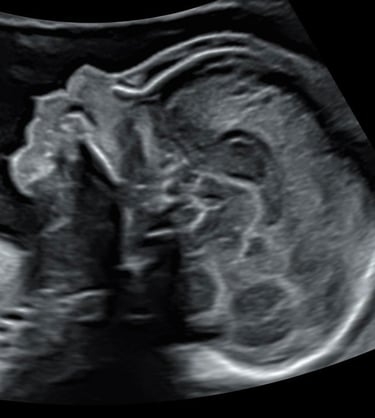

Lors d’une grossesse, l’échographie est un outil indispensable pour le suivi.

Il s’agit d’un examen de dépistage et non d’un diagnostic.